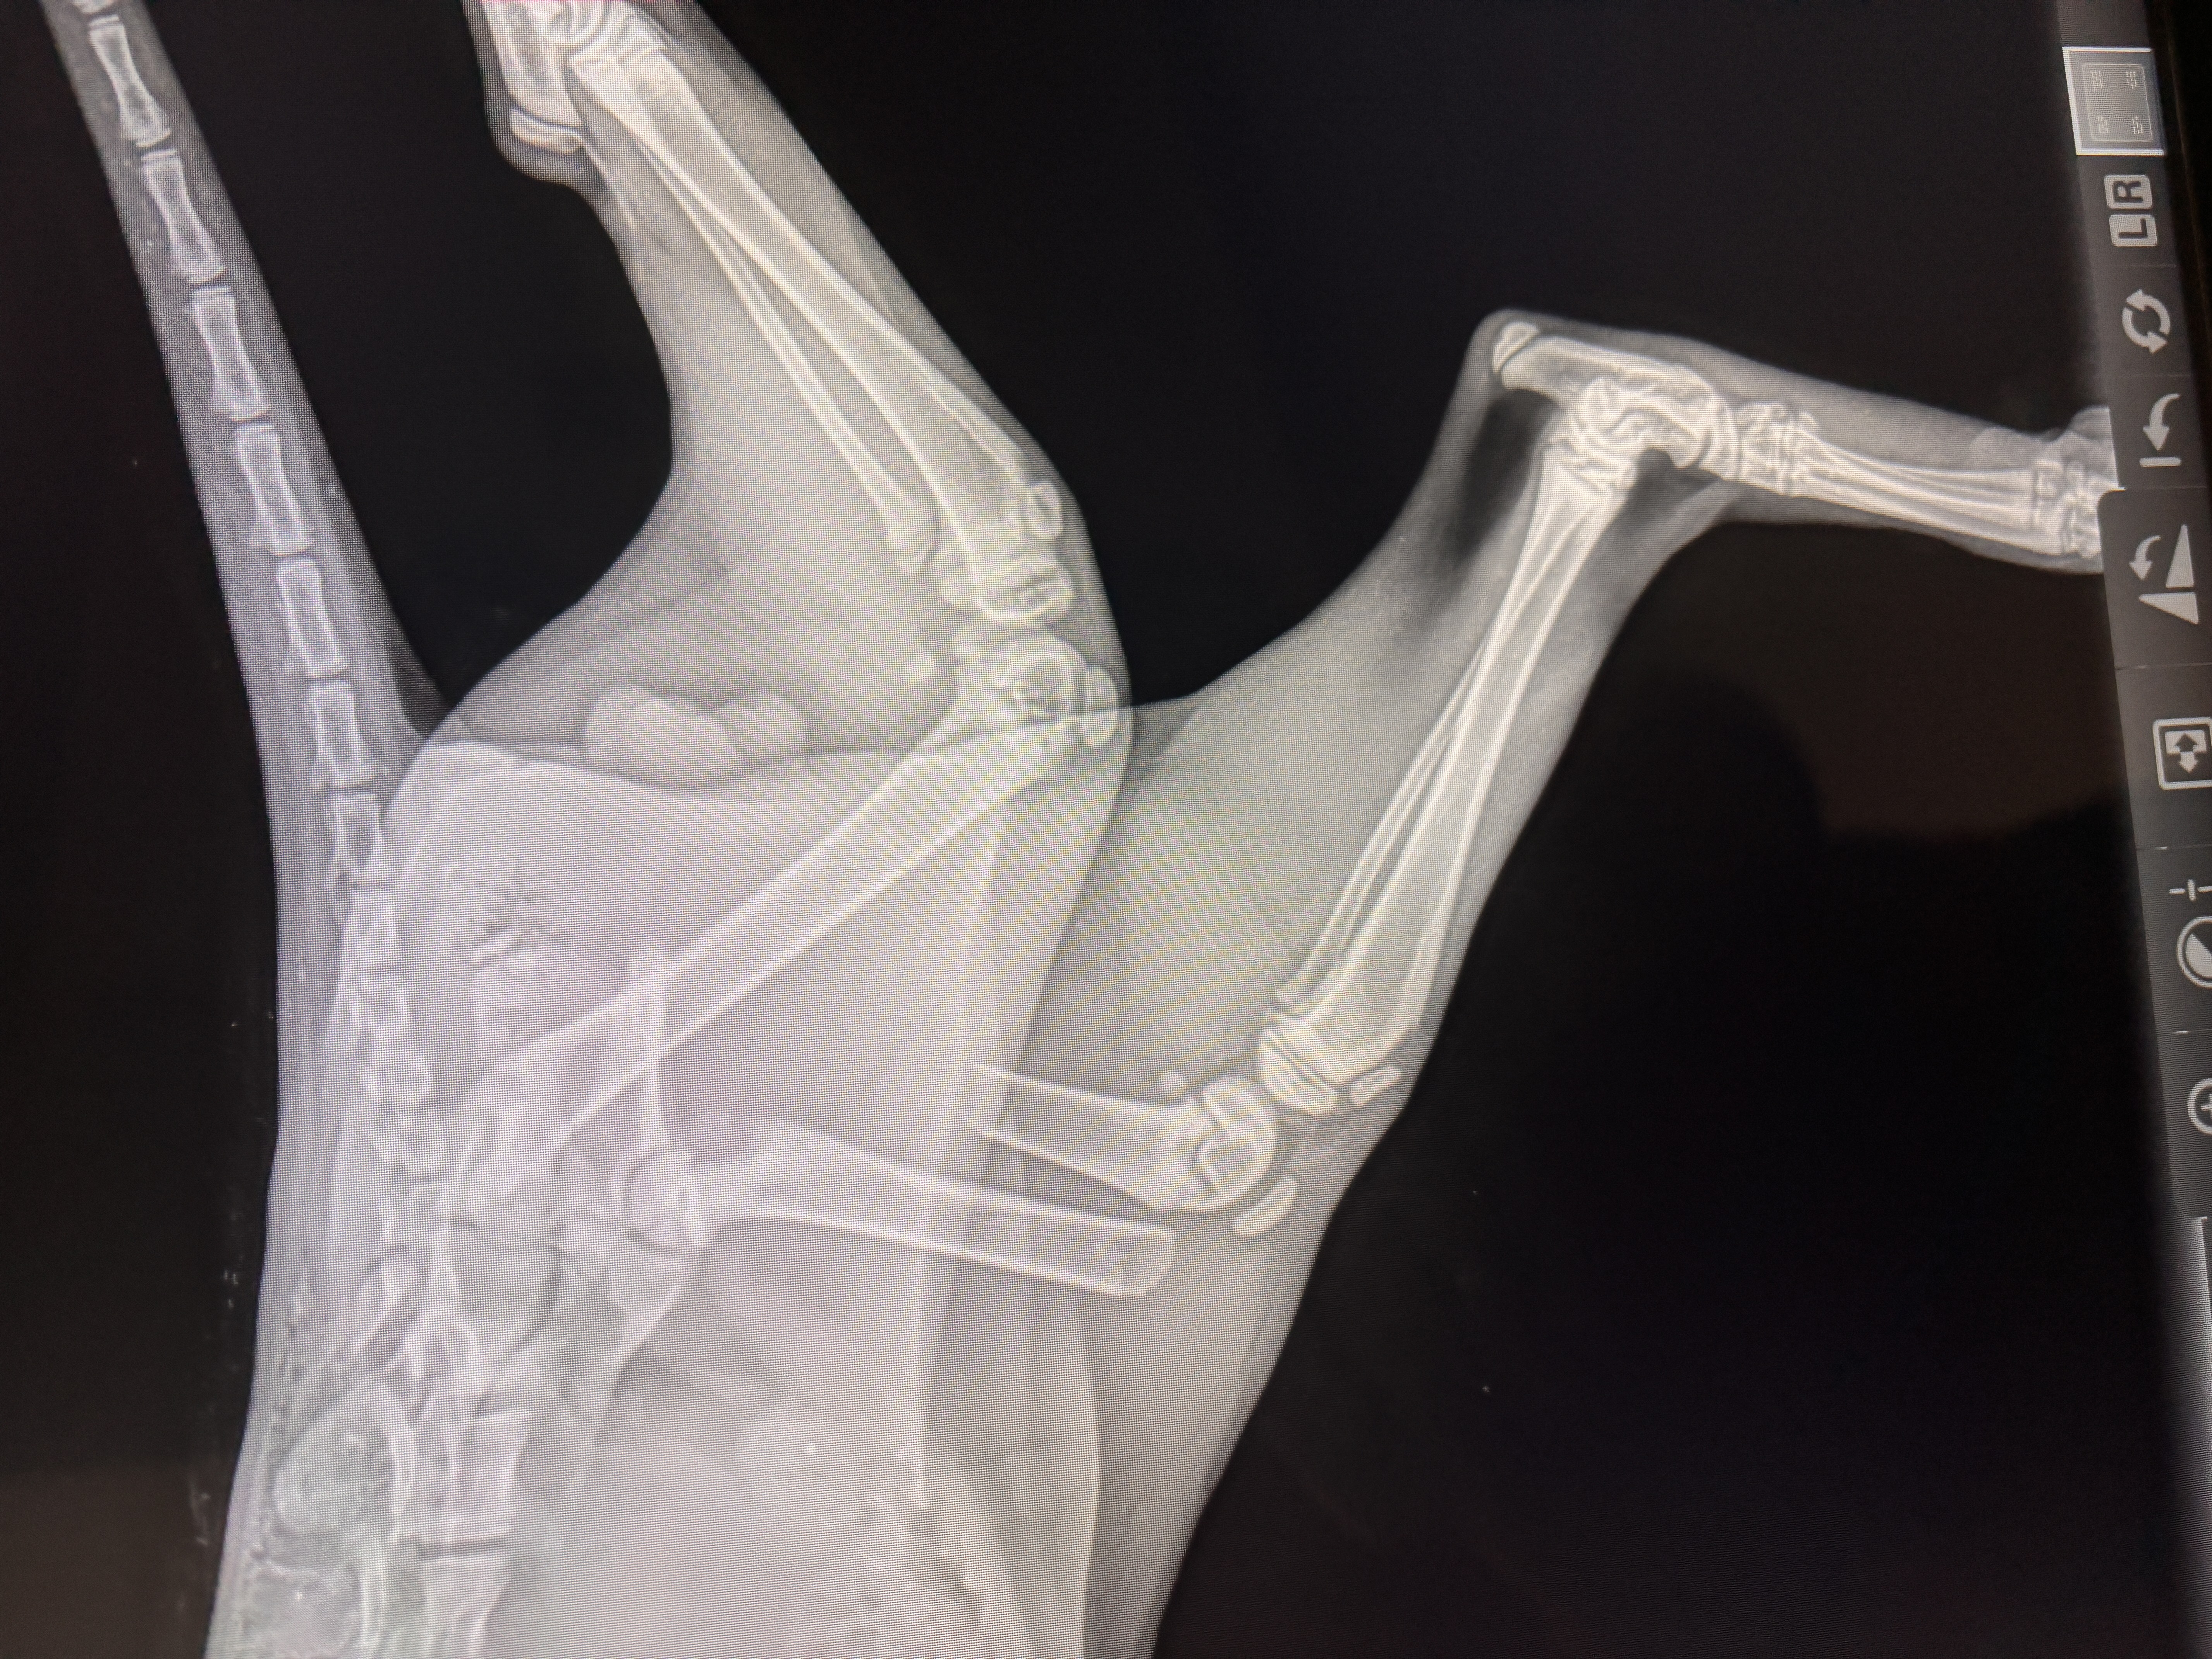

Dragon